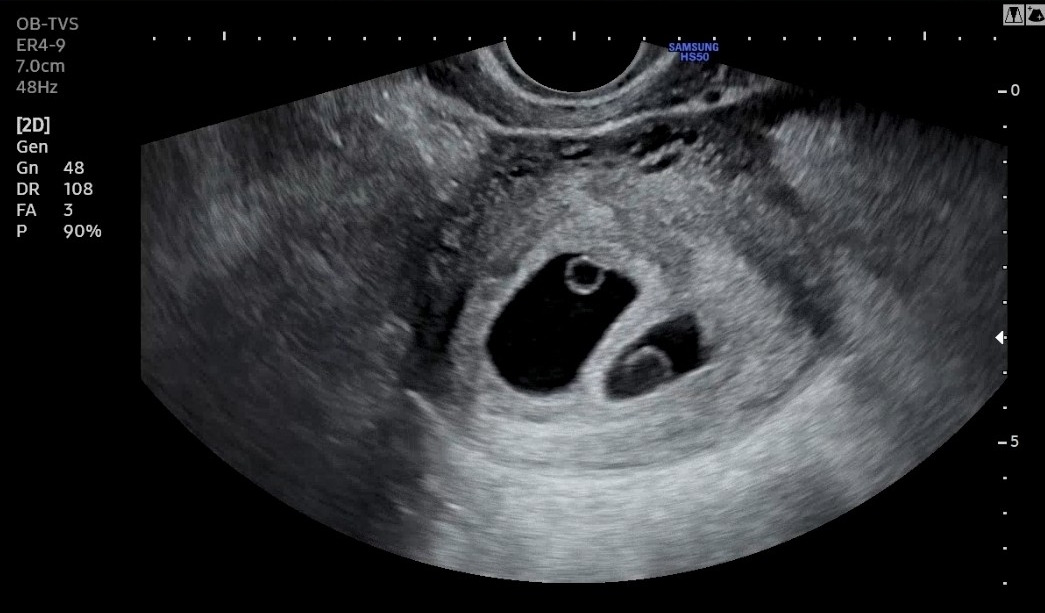

6주 차에 확인한 초음파에서는 지난주보다 훨씬 공간을 늘린 두 개의 아기집과 동그란 난황 2개, 그리고 두 아이의 반짝이는 심장까지 볼 수 있었다.

반지처럼 동그란 것이 난황이고 그 끝에 붙어있는 게 아기라고 하는데, 내 눈으로는 잘 식별할 수 없었다. 의사 선생님이 여기서부터 여기까지가 아기라고 화면에 표시해 주시며, 머리부터 엉덩이까지의 길이가 한 명은 0.6cm, 한 명은 0.48cm라고 했다.

"그런데 한 아이가 난황이 좀 크네요. 난황이 크면 예후가 좀 안 좋기도 하거든요. 먼저 생긴 아기는 난황 크기가 적당한데, 나중에 생긴 아기 난황 크기가 좀 커 보여요. 그래도 두 아이 모두 심장은 잘 뛰어요. 난황 크기보다 심장 뛰는 것이 더 중요하긴 한데.. 그래도 조금 지켜보아야 할 것 같아요. 다음 주에 한 번 더 오세요."